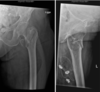

En 72 årig mand er faldet i hjemmet. Røntgen viser nedenstående

Hvilken af følgende udsagn er KORREKT

- a. Frakturen er intraartikulær

- b. Frakturen er pertrochantær

- c. Frakturen er simpel

- d. Der er vinkling, men ingen forkortning i frakturen

- e. Patienten bør opereres med en protese

*c. Frakturen er simpel

- Note:*

- a. Nej - det kan man tydeligt se*

- b.Nej - jeg vil mene den er subtrochantær*

- c. Ja - der er kun 2 fragmenter*

- d. Der er vinkling, men også forkortning*

- e. Nej - hvis der havde været samtidig dislokation havde man opereres med en protese*